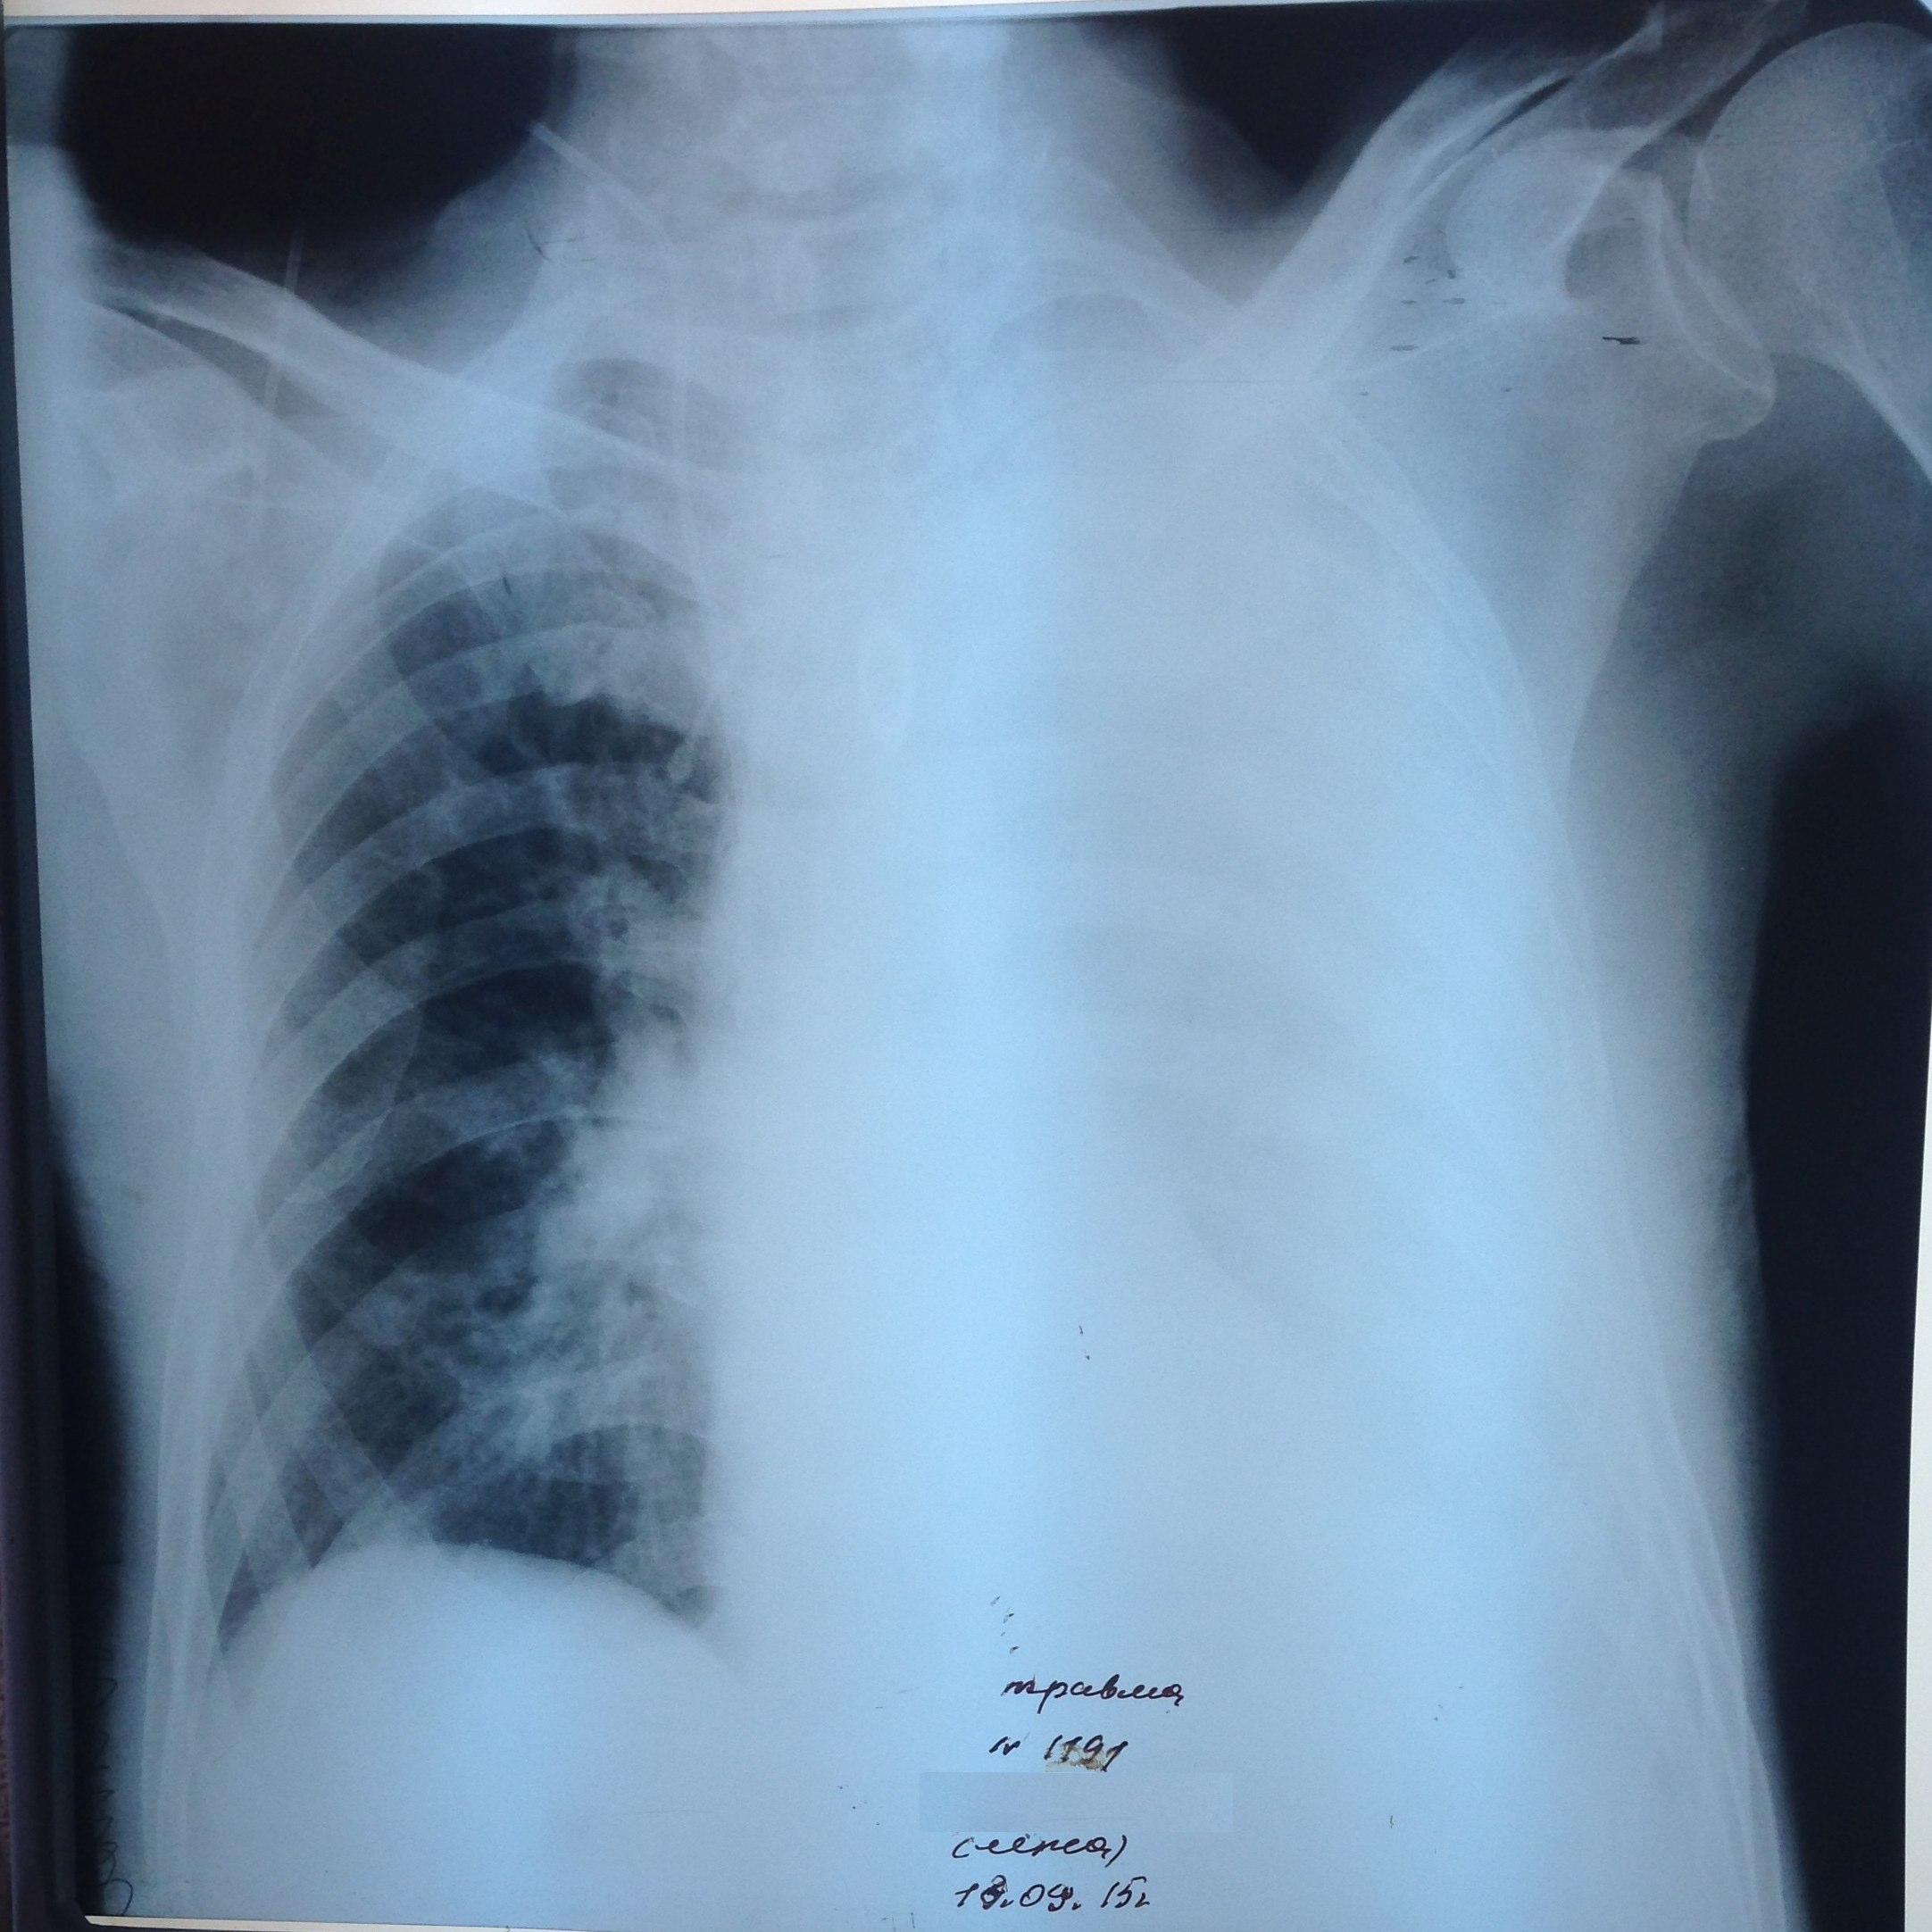

Левосторонний тотальный гемоторакс у женщины с раком правой молочной железы с метастазами в оба легких. Первый снимок при поступлении и после удаления 4 литров геморрагической жидкости.

Обсуждалось в Госпитале Ослабленных Сердец